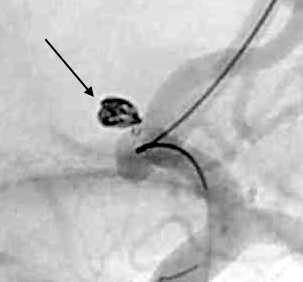

脳動脈瘤は脳にできた「血管のこぶ」であり、破裂すると「くも膜下出血」という生命を脅かす重大な病気にあることがあります。脳ドックなどで発見されて破れる前に手術をすることもあり、破裂しても再破裂を予防する目的で手術を行います。血管内治療では動脈瘤の中にコイルと呼ばれる柔らかい金属を詰めて固めることにより出血を予防することが可能で、開頭術と比べ遜色のない有効性と安全性が確立されています。その際にはステントや風船(バルーン)を使って正常の血管を塞栓しないように工夫をすることで安全性を高めています。